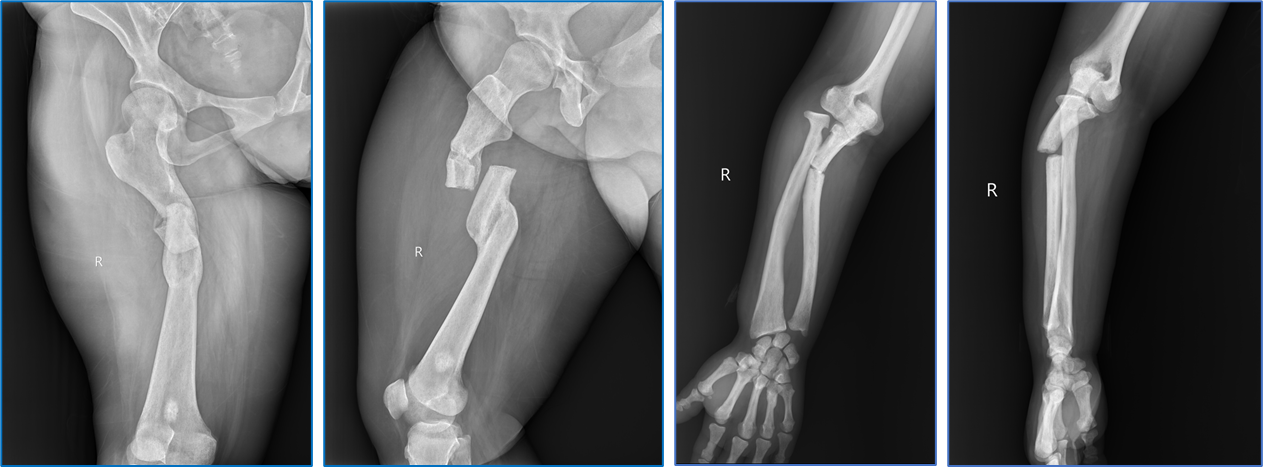

图1右侧股骨、左侧肱骨骨折X线片(受伤后约16月)

陈某是一位38岁的女性脆骨病患者,据她讲述,出生到现在记忆深刻的骨折发生了8次之多。最近一次发生在2023年5月,她在平地滑倒之后,导致了右侧股骨、右侧尺骨及左侧肱骨骨折,当地医院考虑到患者疾病的复杂性,给予患者保守治疗。之后按时定期复查,骨折一直没有愈合迹象。反复就诊于多家医院,都未能得到解决,患者几近绝望,看着自己正值需要照顾的孩子,更是心急如焚。经在网上查询及向周边人打听,患者找到了我院骨病与创伤病区张纯主任,鉴于在骨病与创伤治疗方面的丰富经验,张纯主任在详细了解病人病情后将患者收住入院,并积极开展全科讨论。骨病与创伤病区全体医生纷纷献计献策,最终讨论意见一致,同意给予患者内固定手术治疗。张纯主任、高宗强主任医师以及李永伟博士认真查阅文献,反复对患者肢体及影像学资料进行测量,还利用现有内固定物进行手术模拟,从而制定出详细的术前计划;吴玮护士长将该患者列为重点护理对象,责任护士杨小红认真总结手术前后的护理要点,并提前与手术室详细沟通病人转运期间的细节及注意事项,以确保手术万无一失。一切准备就绪后,在张珍妮、镇路明两位麻醉医生的保驾护航下,为患者实施了右侧股骨及肱骨钛板内固定术。赵丽燕护士长全程关注手术进程,及时应对术中需求。得益于前期的精心准备及术中各方的密切配合,手术进行得非常顺利,患者股骨及肱骨终于完成了“续骨”。麻醉苏醒后,患者眼含泪水,对张纯主任说的第一句话:“感谢张主任,给了我第二次生命”。在此中秋佳节之际,张纯主任不仅让患者分离一年多的骨头得到了“团圆”,更是让患者饱受折磨和焦虑的心得到了慰藉。